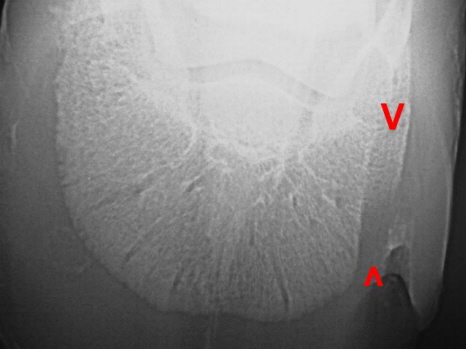

Hornsäule